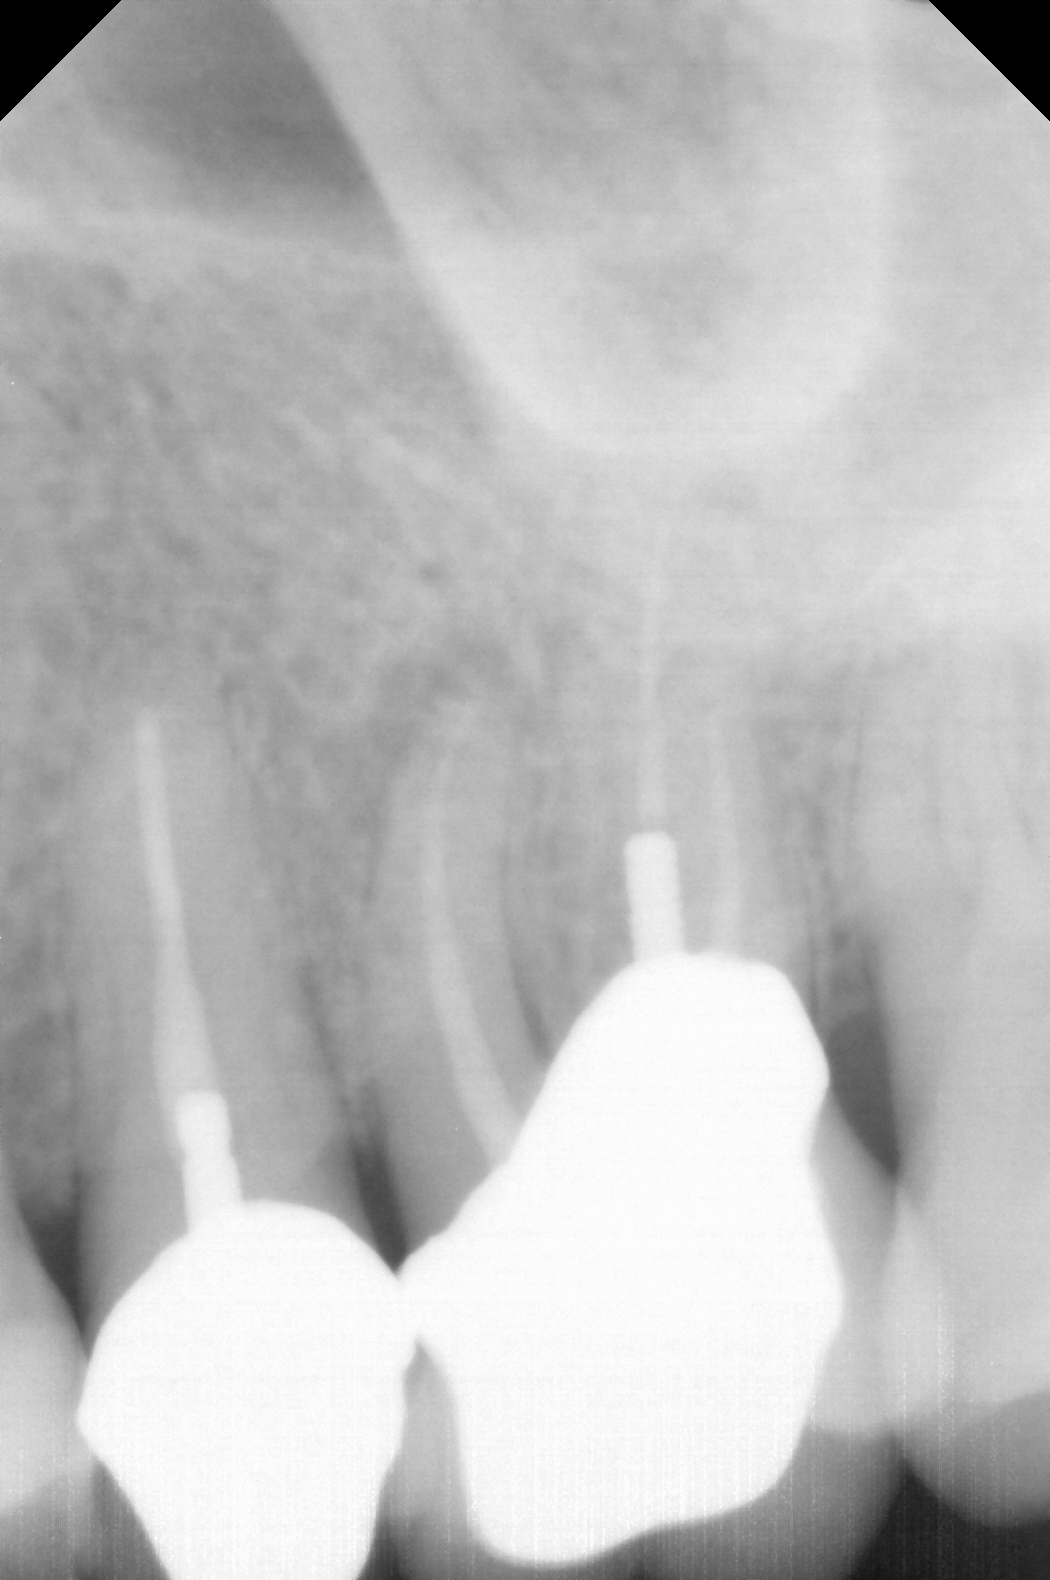

Fig 4. Preoperative radiograph showing aggressive external root resorption and thin dentinal walls.

Figure 4

Fig 5. Working length confirmation.

Figure 5

Fig 6. Postoperative radiograph.

Figure 6

Fig 7. 1-year follow-up showing a healthy lamina dura and root development.

Figure 7

Fig 8. 3-year follow-up showing continued root development.

Figure 8